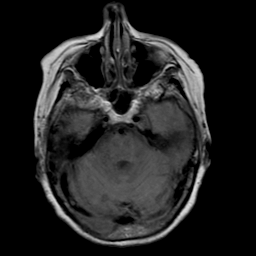

Stroke: proton density-weighted MR #2 -- Slice #6

[Home][Help][Clinical] Slice 6